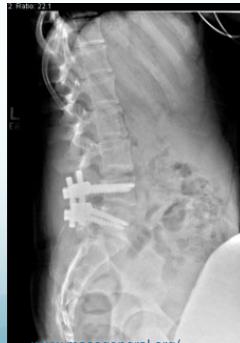

Diagnostic Imaging

- Lateral view: Shows vertebral slip

Operative (Spinal Fusion):

- Young patients with severe symptoms

- Neurological symptoms present